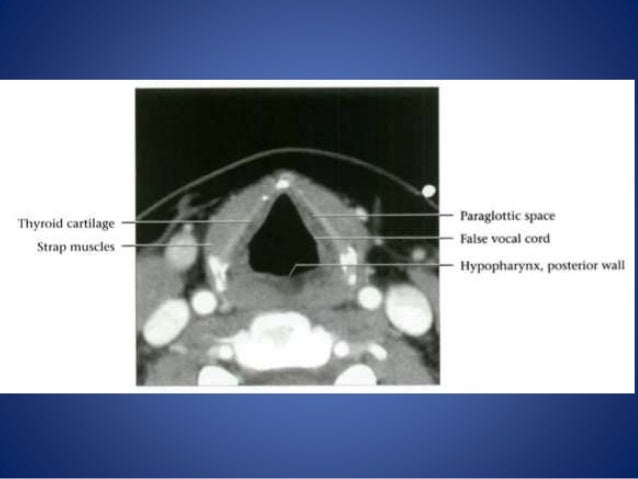

Head And Neck Anatomy | Radiology Reference Article | Radiopaedia.org

neck radiopaedia

Larynx Anatomy And Laryngeal Carcinoma

larynx laryngeal commissure sinus carcinoma